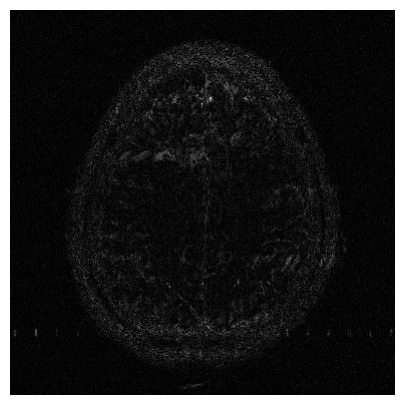

Qualitative.

The visual inspection of the images reconstructed (available in Fig. 2) at acceleration factor 4 shows little to no visible difference with the ground truth original image. However, when increasing the acceleration factor to 8, we can see that smoothing starts to appear which leads to a loss of structure as can be seen in Fig. 3.

| T1 PSNR: 41.56 SSIM: 0.9506 | T2 PSNR: 40.68 SSIM: 0.9554 | FLAIR PSNR: 39.60 SSIM: 0.9321 | T1POST PSNR: 42.53 SSIM: 0.9683 |